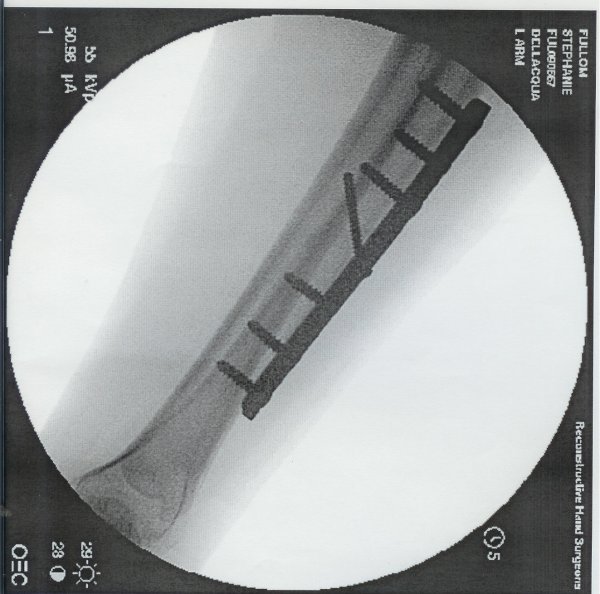

X-Ray with Plate 2 Days after Plate Removal 1 Day Later

Bledsoe Brace Xray with Plate

4 Weeks Post-Op Plate and Screws